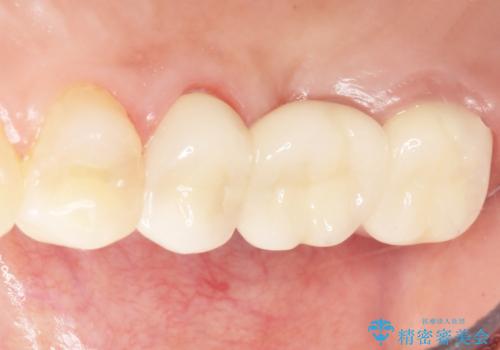

インプラントや入れ歯を使わずに奥歯でしっかり咬むことができるようになり、また見た目も自然だと大変喜んで頂けました。

クラウンの種類:メタルボンドクラウン エコノミー フルベイク